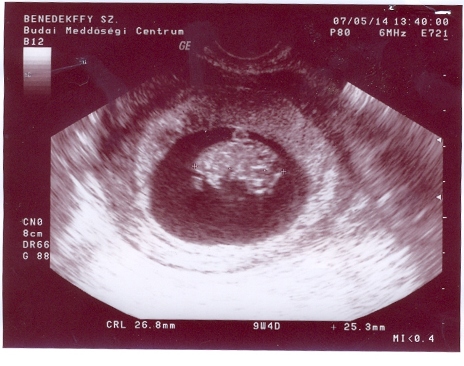

Nem tüntem el, csak időm nincs a 2 gyerek mellett. Mi lesz ha meg lesz a 3.

Benszi!

Nagyon jók az Uh képek. Én most nem kaptam, de ezek után se fogok kapni, mert videóra vesszük majd fel, másik 2 fiam is így van megörökítve.